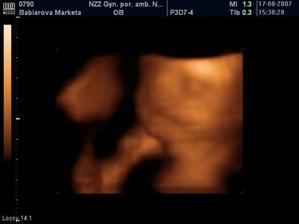

Naše bábätko

Začala sa moja cesta vývinu a mal by som prísť na svet 1.12.07.